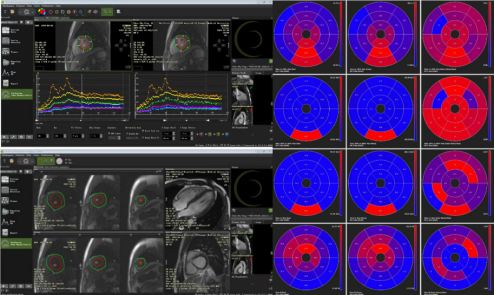

负荷心肌灌注检查增加了心肌微循环障碍患者的检出率,同时我院放射学科可通过后处理软件对微循环障碍进行定量及半定量分析(图2)。负荷心肌灌注可应用于冠状动脉交界性狭窄患者、冠状动脉狭窄<50%的患者以及非缺血性心肌病患者评估其是否存在微循环障碍,是目前检出心肌微循环障碍的可靠且无创的检查方法,可为心内科医生对这类患者进行个性化治疗提供客观依据和疗效评价。

图2